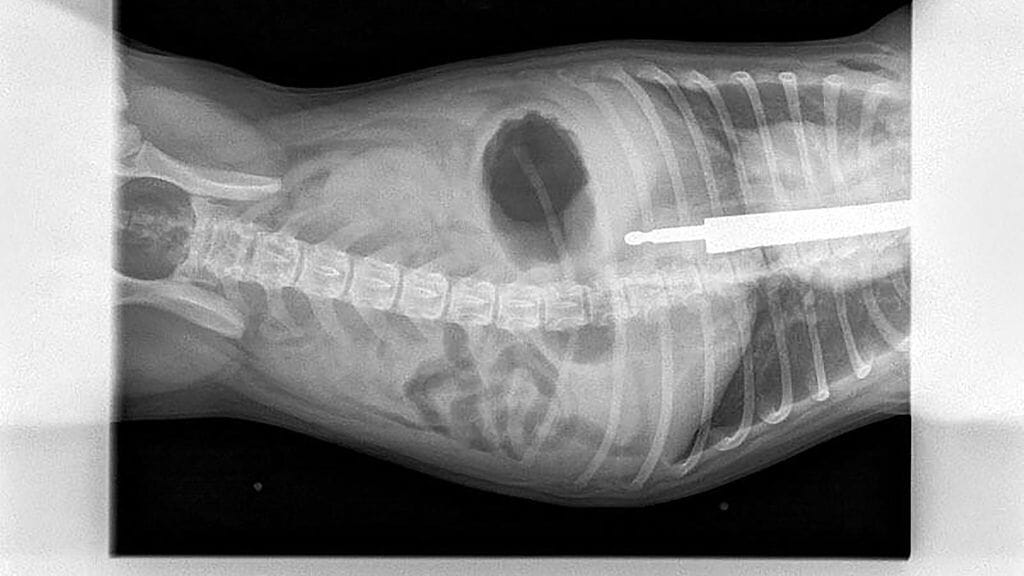

Omistajat kertoivat huomanneensa, että Lexi oli kärsinyt vatsakivuista. Eläinlääkäri otti Lexistä röntgenkuvan, josta selvisi, että hänen vatsassaan on noin 20 senttimetriä pitkä veitsi.